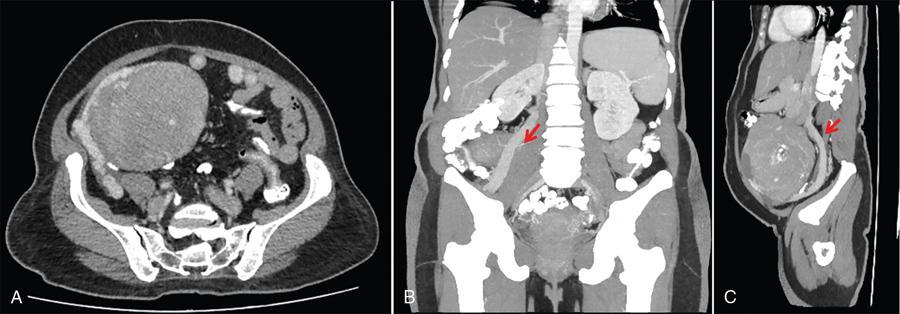

Suriyaprakash Nagarajan, Rupa Renganathan, Suhasini Balasubramaniam, Anupama Chandrasekharan, Kumarsampath Sumeena OVARIAN CYST VERSUS BLADDER Cystic lesions are common in female pelvis and mostly they originate from ovary. Ovarian cysts can arise from epithelial, stromal or germ cell components and can be benign or malignant cystic lesions. Pelvic Ultrasonography (USG) is the preferred imaging modality for evaluation of adnexal cystic lesions. Large simple ovarian cyst appears unilocular, anechoic with thin smooth walls. Such large simple cysts are confused with distended bladder. Distended bladder is a condition in which the urinary bladder is full and the patient is unable to void completely causing abdominal discomfort and pain. Distended bladder can be due to obstruction to passage of urine, neurological disorder or spastic sphincter. Differential diagnosis of cystic lesions in pelvis can be intraperitoneal, extraperitoneal and both intraperitoneal and extraperitoneal. Cystic lesions of intraperitoneal origin includes peritoneal inclusion cyst, paraovarian cyst, mucocele of appendix and hydrosalpinx. It is important to differentiate large simple ovarian cyst and distended bladder when patient presents with lower abdomen pain and the patient’s clinical history helps to make an accurate diagnosis (Table 11.4.1.1). UTERINE VERSUS EXTRAUTERINE MASS Ultrasound is usually the initial imaging modality for the pelvic mass. When USG findings are indeterminate to ascertain the organ of origin and to characterize, the next imaging modality is MRI due to its superior soft tissue resolution and multiplanar imaging capability (Figs. 11.4.2.1 and 11.4.2.2). Signs are demonstrated in Figs. 11.4.2.3 to 11.4.2.6. The sequences used in MRI pelvis are conventional T2WI in all three planes and T1WI in single plane. The problem-solving sequences are oblique coronal and oblique axial T2 along and perpendicular to the long axis of uterus in sagittal localizer. It can identify the organ of origin. Other sequences like T1 fat sat, diffusion-weighted imaging (DWI) and dynamic contrast T1WI with fat sat and subtracted images help to characterize the lesion further. BLADDER MASS VERSUS PROSTATE MASS Irregular mass lesions in the bladder neck are termed as ‘Bladder occupying lesions’. It is often difficult to determine whether the origin of these lesions is the bladder or the prostate gland. Transabdominal Ultrasound with colour Doppler studies and CT imaging do not usually delineate the origin of the lesions. The following features may aid in the differentiation (Table 11.4.3.1): History Painless haematuria Usually asymptomatic Investigations TAS, TRUS, MRI, Cystoscopy-guided biopsy PSA, DRE, TRUS, MRI, TRUS-guided biopsy At what point is the cross over between the two lesions T4 bladder cancer invading the prostate Aggressive prostate cancer protruding into the bladder Epicenter of the lesion Within the bladder Within the prostate gland Central necrosis in the mass Not commonly seen Seen in sarcomas IVU/CT urography Additional lesions in the urinary tract suggest that the bladder occupying mass in the bladder neck is of bladder-origin Prostate masses do not commonly cause masses in the urinary tract except for the very rare metastasis Virtual cystoscopy Additional lesions in the bladder wall and dome suggest that the bladder occupying mass in the bladder neck is of bladder-origin MRI T2 hypointensity Bladder masses are usually T2 hyperintense Seen in adenocarcinomas MRI T2 hyperintensity Bladder masses are usually T2 hyperintense Urothelial tumours infiltrating the prostate, neuroendocrine masses MRI T1 and T2 hyperintensity Bladder masses are usually T1 hypointense and T2 hyperintense Mucinous adenocarcinoma MRS Elevated choline values are seen in highly cellular masses Elevated choline:citrate ratio in prostate malignancies No significant finding in mucinous adenocarcinoma DWI Diffusion restriction is seen in malignant bladder masses No restriction in mucinous adenocarcinoma BPH versus bladder mass Exophytic BPH has signal intensities and appearance similar to and is contiguous with BPH within the gland OVARIAN MASS VERSUS PARAOVARIAN MASS Ultrasonography (USG) is the primary imaging modality in patients presenting with pelvic symptoms. Transvaginal, transabdominal or both should be performed in evaluation of such patients to differentiate ovarian and nonovarian origin of the lesions. Ovarian lesions can be a simple ovarian cyst, complex cyst with septations and solid components or a solid mass. Paraovarian lesions are remnants of the Wolffian duct in the mesosalpinx along fallopian tube or the ovaries and do not arise from the ovary. Paraovarian cysts are classified based on their site of origin into paratubal mesosalpingeal cysts, hydatid cysts of Morgagni, paraovarian cystadenoma and subserosal cysts. Differentiation of ovarian and paraovarian lesion poses significant diagnostic challenge. Both Computed tomography (CT) and Magnetic resonance imaging (MRI) are essential problem-solving tool in determining the site of origin of a pelvic mass. The first step in pelvic mass evaluation is to find out if it is ovarian or nonovarian in origin. Characterization of paraovarian or ovarian lesions is of utmost importance in order to optimize therapeutic procedures and it influences patients management (Figs. 11.4.4.1 and 11.4.4.2). Findings such as ovarian vascular pedicle sign, claw sign, bird beak sign and visualization of normal ovary helps to differentiate between ovarian and paraovarian lesions. Subsequently ovarian lesions should be categorized into benign, indeterminate and malignant masses (Table 11.4.4.1).

Ovarian cyst in plain radiograph is noted on one side of the pelvis. Areas of calcification can be demonstrated.

Plain radiograph (Fig. 11.4.1.1) shows a midline opacity arising from the pelvis extending above the pubic symphysis which gets relieved on catherization.

Bladder is visualized as a round or oval shaped anechoic fluid filled structure in the midline of pelvis (Fig. 11.4.1.3A).